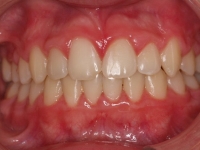

Paciente de 13 años que presenta sonrisa disarmónica.

- Clase I esquelética

- Clase I molar

- DDM +++ anterior

- Sobremordida

Decidimos extraer los 4 primeros premolares.

A los dos años quitamos aparatología fija y la paciente entra en fase de contención encantada con su nueva sonrisa.

Lleva férulas ESSIX a la noche más una contención fija inferior de canino a canino.